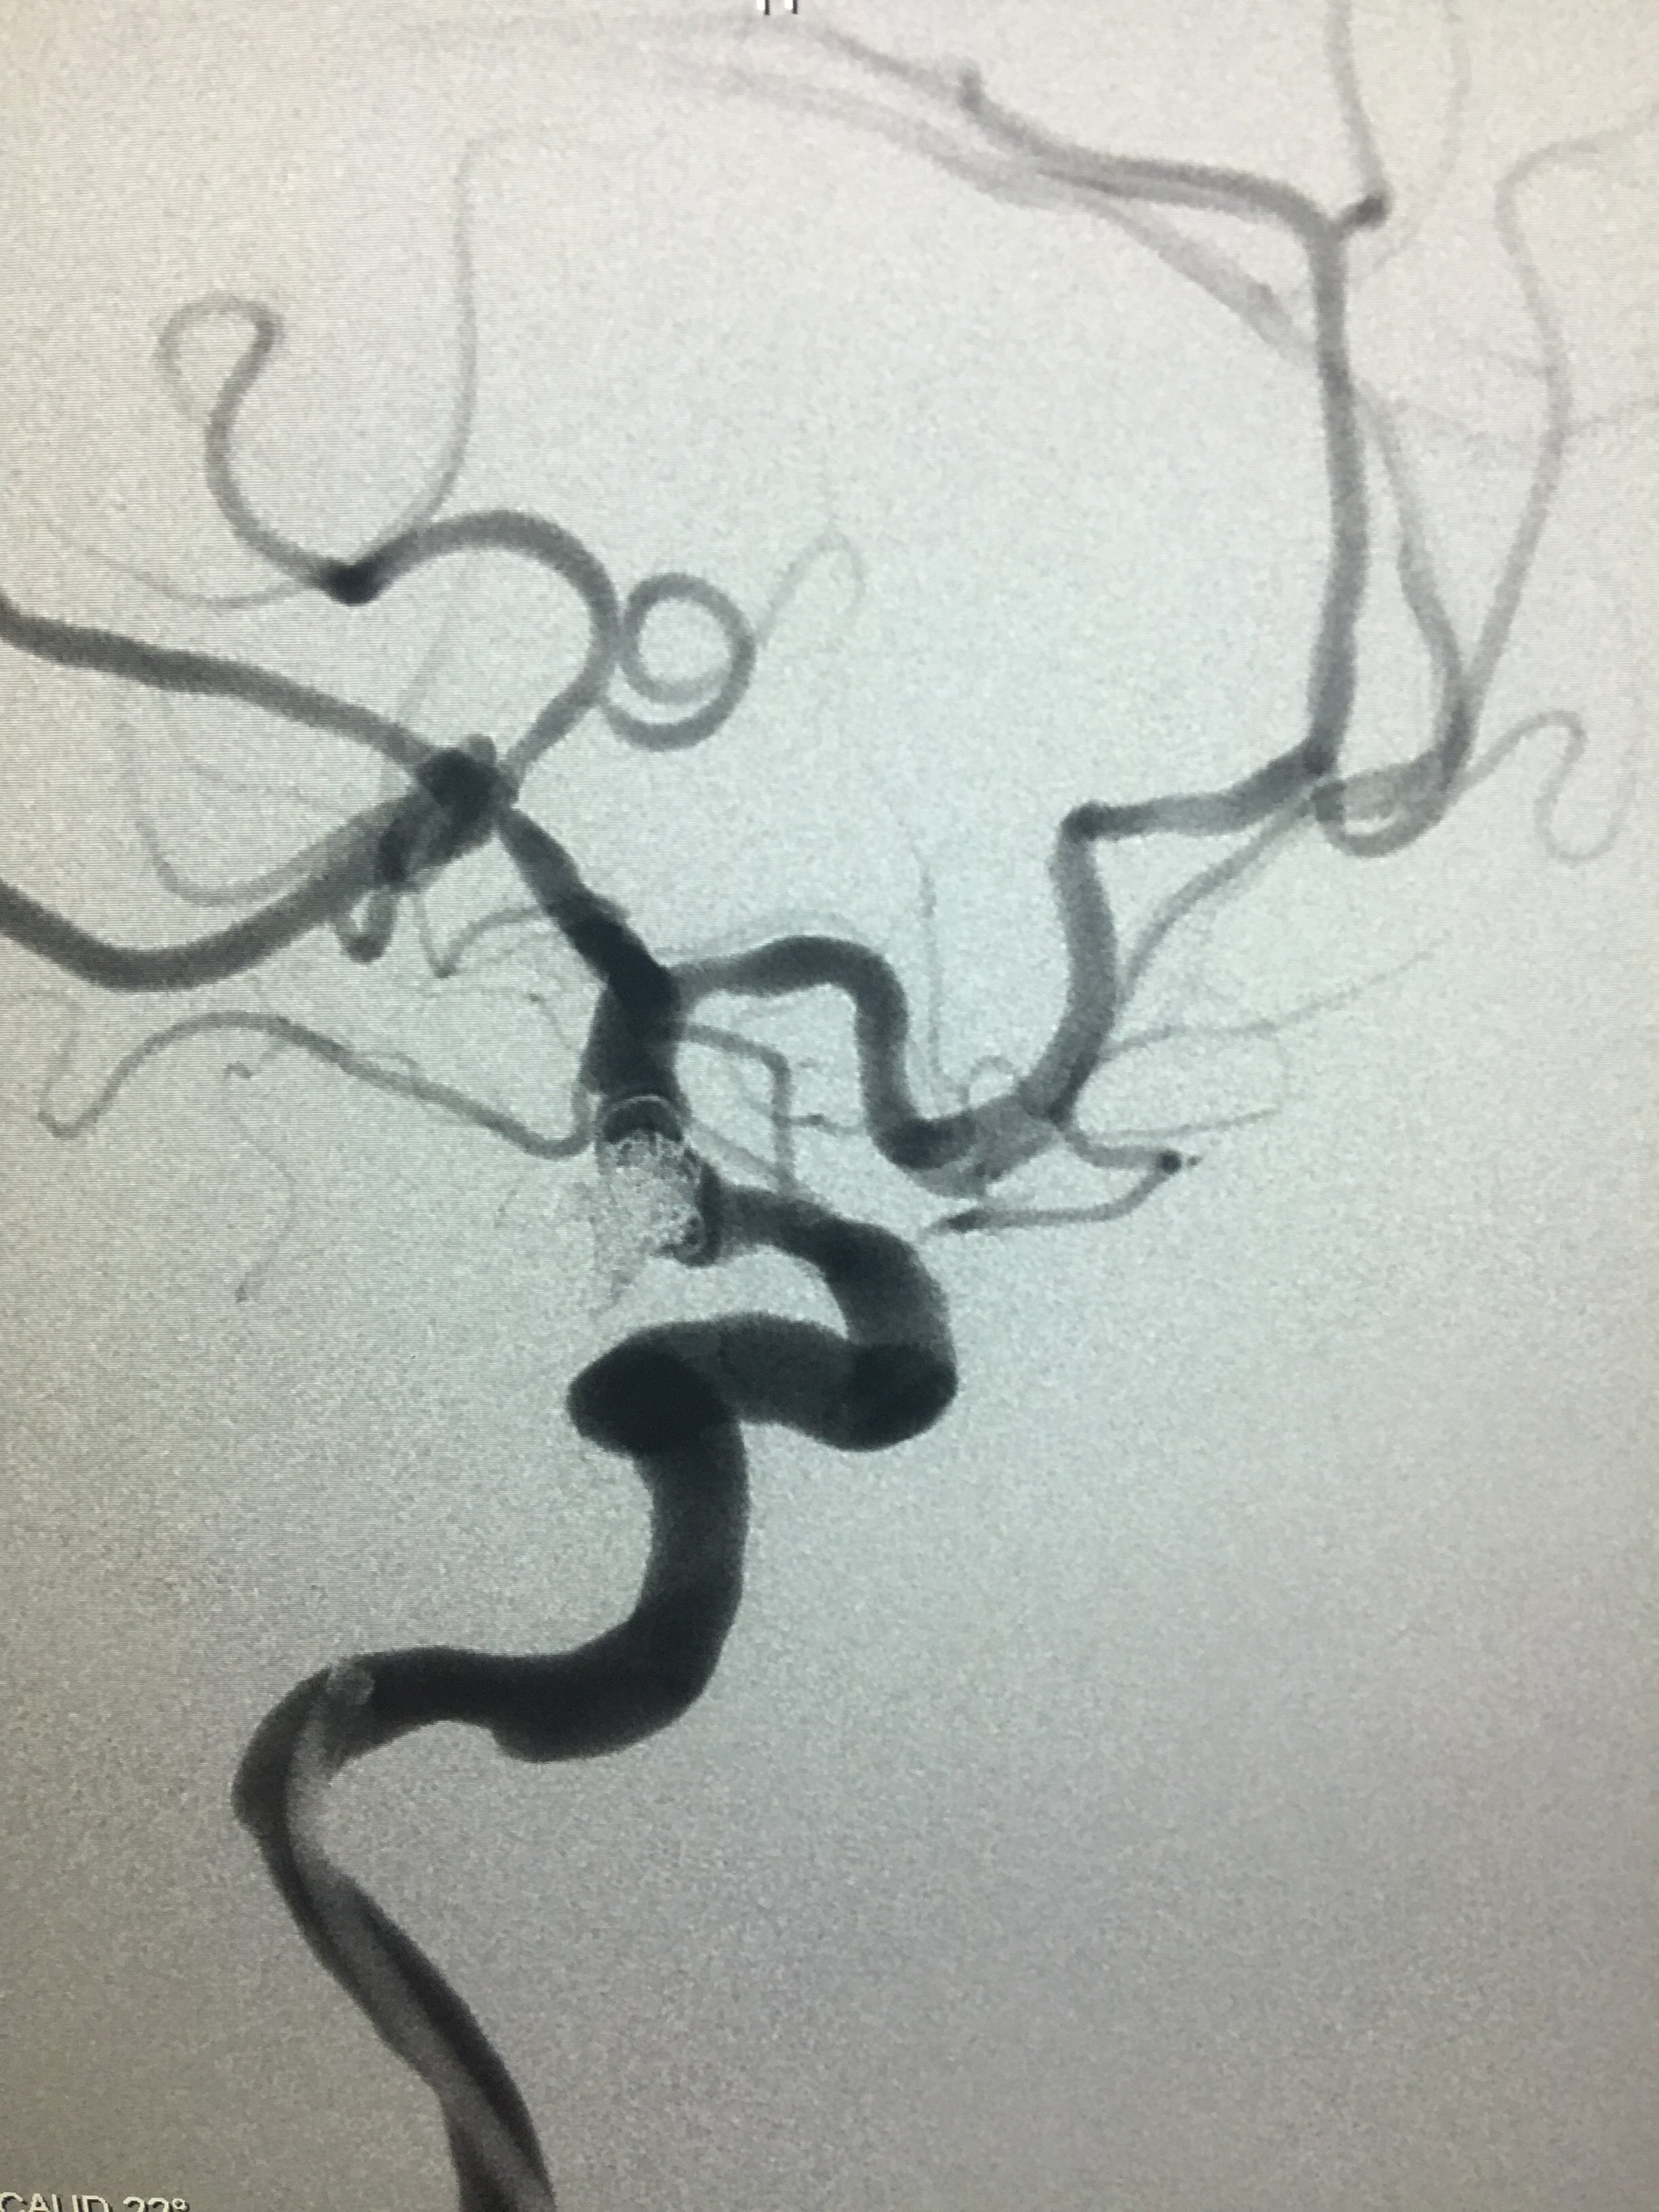

病例六:右侧后交通多发动脉瘤

支架辅助栓塞